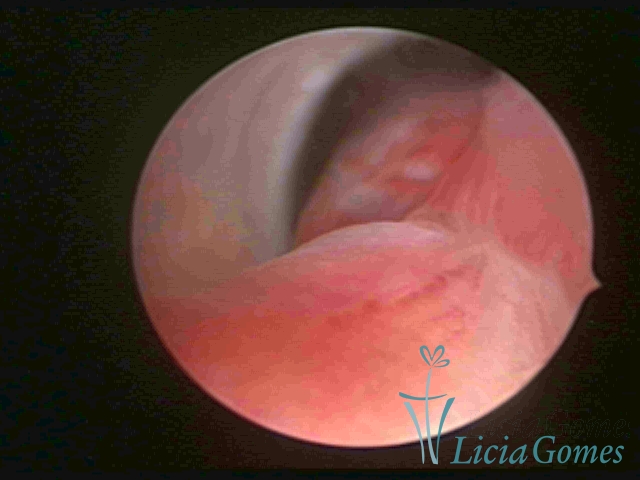

PÓLIPOS ENDOCERVICAIS

São tumores benignos, resultantes da proliferação focal reativa aos processos inflamatórios ou à situações de hiperestrogenismo, e podem ter sésseis (com a base de implantação larga) ou pediculados do epitélio.